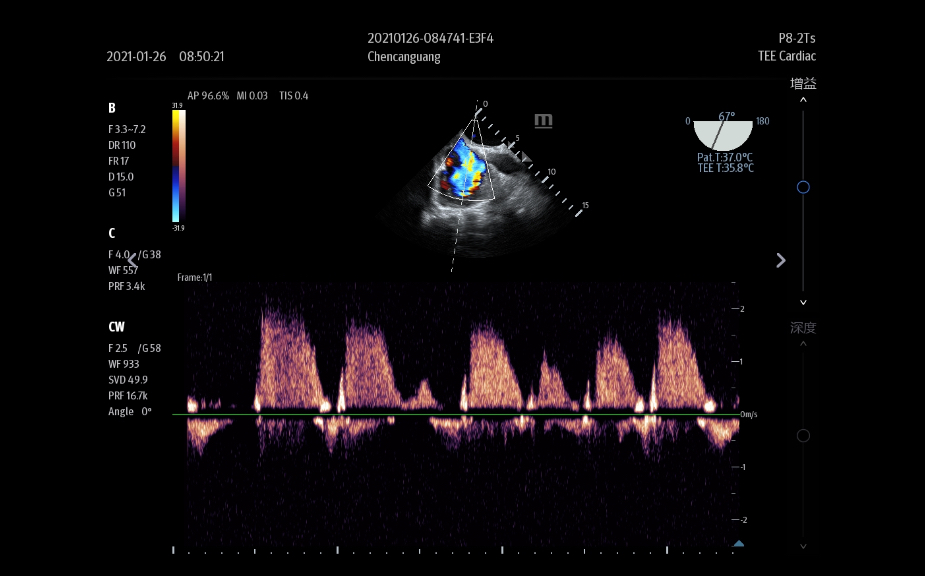

Images

Transducers